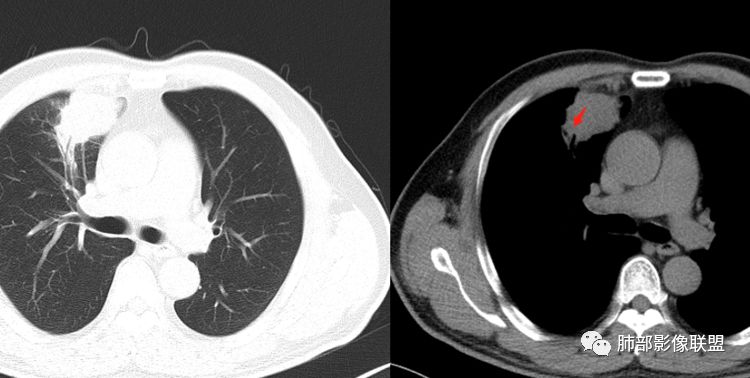

甄德强:这个是炎症,治疗一月后复查图片。

Coke with ice:薄层很重要,要不然好多征象都是靠感觉。

回顾性分析本病例,小编觉得鉴别诊断聚焦于肺鳞癌和炎性病灶(包括结核)之间,这个病灶的炎性征象大于恶性征象;以下是这个病例的的炎性征象:①病灶边缘平直收缩为主,也缺少典型的分叶毛刺;②支气管走行于病灶中央截断,断端比较圆钝;③近端引流支气管壁增厚;④整体强化不显著,坏死区太圆太规整,边缘隐约显示强化的环;⑤血管走形自然,未见明显破坏征象;⑥胸膜外脂肪间隙增宽,胸膜广基地增厚,未见栽赃;⑥52岁偏年轻(此条也不大支持鳞癌)

虽然本例患者支气管截断,病灶中央截断炎性及恶性都可以,断端向病灶一侧圆钝更支持炎性。